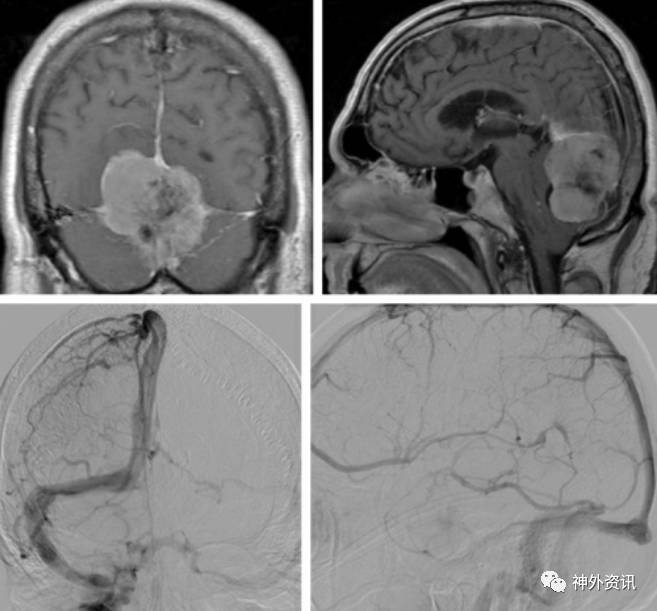

图1. 若肿瘤侵袭窦汇则将显著增加手术切除时空气栓塞的发生风险。因此,我强烈推荐在此类以及类似于需暴露硬膜窦的手术时运用经食道和心前区多普勒超声进行监测。